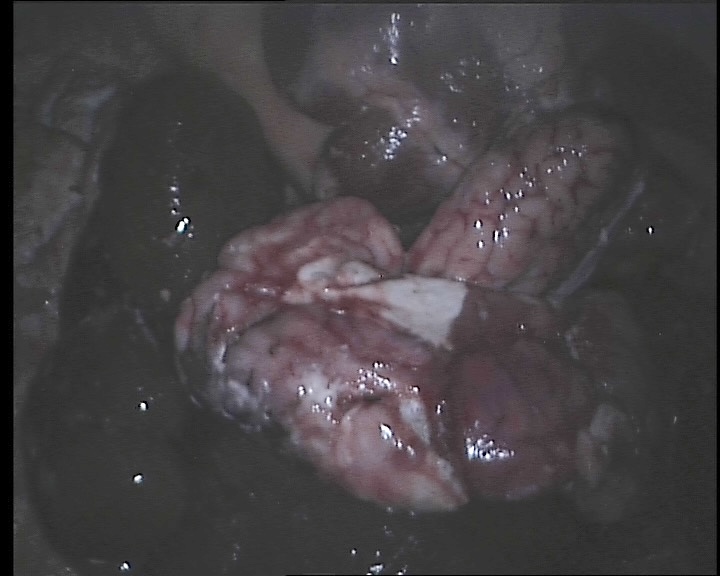

(a) The capture of a sheep’s liver using the dVRK laparoscope.

Refer to caption

(b) An example image captured which contains multiple ex vivo tissue.

Figure 2: Shown in (a) and (b) is the setup for the medical dataset collection. Image (a) shows an example of tissue captured using the dVRK laparascope. (b) does not contain projection patterns and would be fed as an input to the neural network.

Medical dataset: A medical dataset was created using the da Vinci Research Kit (dVRK) (Kazanzides et al. 2014) to extend the evaluation of the model onto real images. The dVRK was chosen as it is the research model of the surgical system that is used in clinical practice and commonly used for research in this field. A structured light projector was attached to a da Vinci camera arm and the stereo laparoscope of the machine was used to capture scenes with projected patterns on medical phantoms and ex-vivo organs from sheep, cows and chicken. Gray code was used for this dataset with 9 patterns. The decoding was performed using the three phase algorithm (Xu et al. 2022). A turning table was used to hold the objects and were rotated for multiple perspectives. Fig. 2 shows the setup and an example image which would be fed as the input to the neural network (an image without projection patterns).